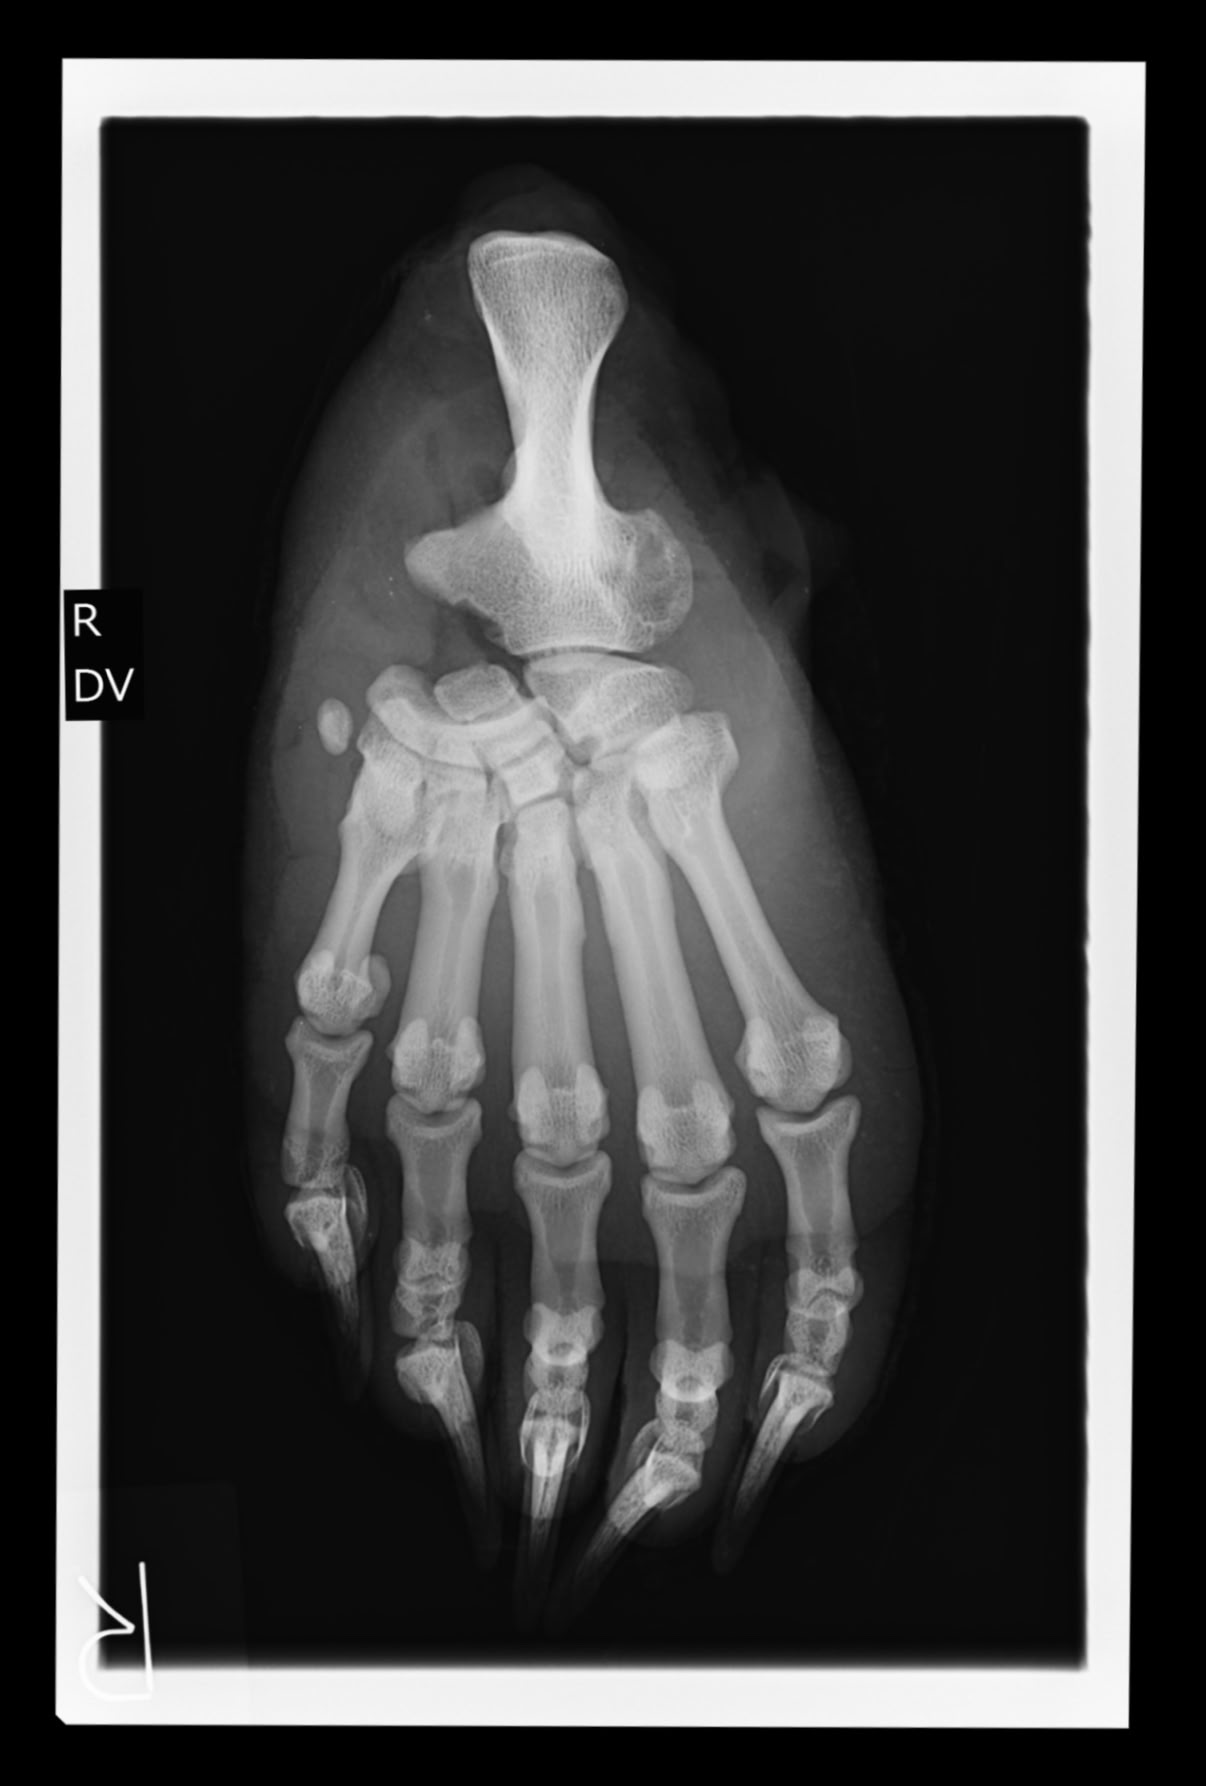

ツキノワグマ右後肢 X線写真(北里大学獣医学部)

2024/1/19